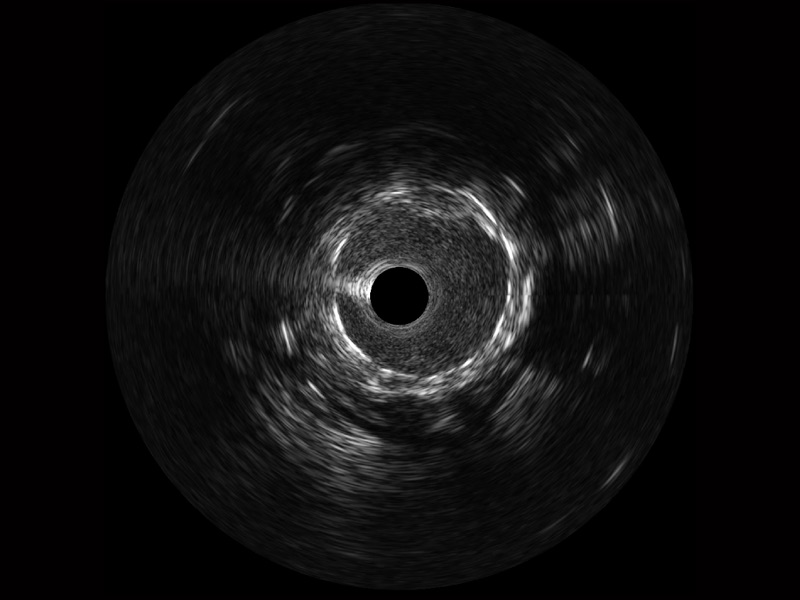

美狮贵宾会官网宽频IVUS图像

传统IVUS图像

对比传统IVUS导管成像,美狮贵宾会官网宽频IVUS图像的近场支架梁显影更细腻,远场中膜外血管仍清晰可辨,兼顾远中近,兼顾分辨力与穿透深度